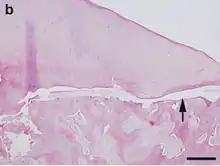

Osteochondrosis is a disease that affects the bone and cartilage in the joints of growing horses. The joints most commonly affected are the fetlocks in the fore- and hind leg, and the hock and stifle of the hind leg. Osteochondrosis lesions include tiny fractures, fluid buildup, loose flaps of cartilage, or chips of cartilage loose within the joint. The last lesion is called osteochondrosis dissecans (OCD), and can develop further into degenerative joint disease, such as osteoarthrosis. Osteochondrosis can also contribute to navicular syndrome and Wobbler disease.[7] Because most horses, especially Hanoverians, which are often used for demanding equestrian sports, work for a living, joint discomfort can mean the end of a horse's career.[8] Between 7% and 10% of Hanoverians have OCD in the hock joint, and between 12% and 24% have OCD in a fetlock joint.[9][10][11]

Recent research has tagged certain conformational characteristics and other heritable factors of bone growth and maintenance as the most important contributors to the development of osteochondrosis.[7] The Hanoverian Breeder's Society in Germany, and all its daughter societies, mandate that stallions must be free of OCD lesions in order to be issued a breeding license. Elite mares and Verband-sponsored auction candidates have identical requirements. Horses are examined with radiographs.